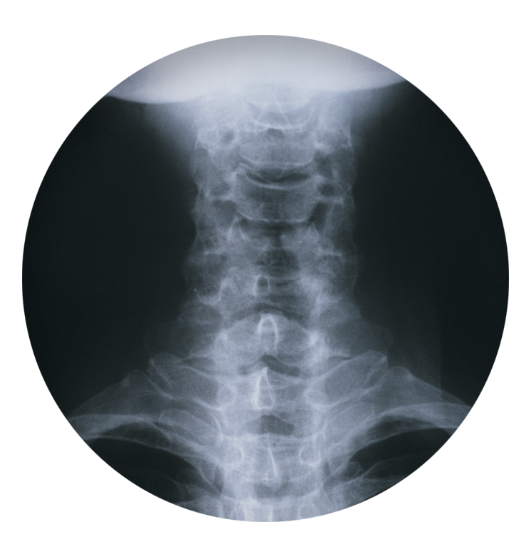

목디스크 치료방법 및 예방방법을 알아봐요 안녕하세요! 오늘은 목디스크 치료방법과 예방법에 대해 알아보려고 해요. 목디스크는 목의 디스크가 손상을 입었을 때 발생하는 질환으로, 목의 통증, 저림, 근육 약화 등을 유발할 수 있어요. 이런 증상을 완화하고 예방하기 위해 정확한 치료방법과 예방법을 알아두는 것이 중요해요.